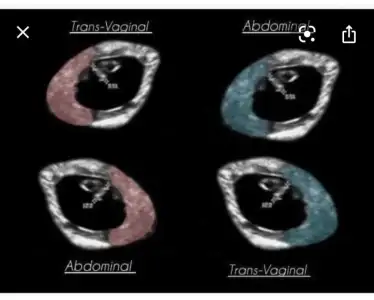

Ramzi teorisini düşünüyorum da, Embriyo ekranda sağ alt köşeye yaslanmıştı... elimizdeki örnekte acaba yine Sağa yatık mı çıkıyor, yoksa sağ sol farkı var mı? Buna göre cinsiyet nedir?

İnsallah daha net de gorursunuz bir sonraki randevuda. Sanirim plasentanin yonune gore yani bebegin saginda mi solunda mi olduğuna gore bakılıyor embriyo yönüne degil de